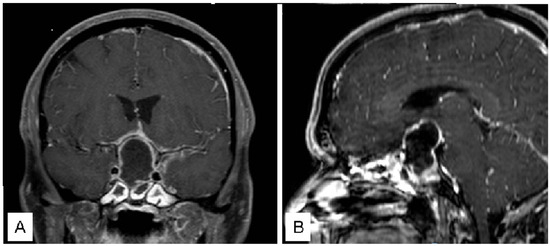

3.1.2. Case 2